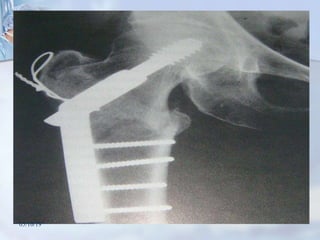

Tratamento cirúrgico

 Melhor método para o tratamento da

maioria das fraturas

transtrocantéricas: (Rockwood e

Sizínio)

 DHS

Tratamento cirúrgico  Melhormétodo para o tratamento da maioria das fraturas transtrocantéricas: (Rockwood e Sizínio)  DHS 05/10/19